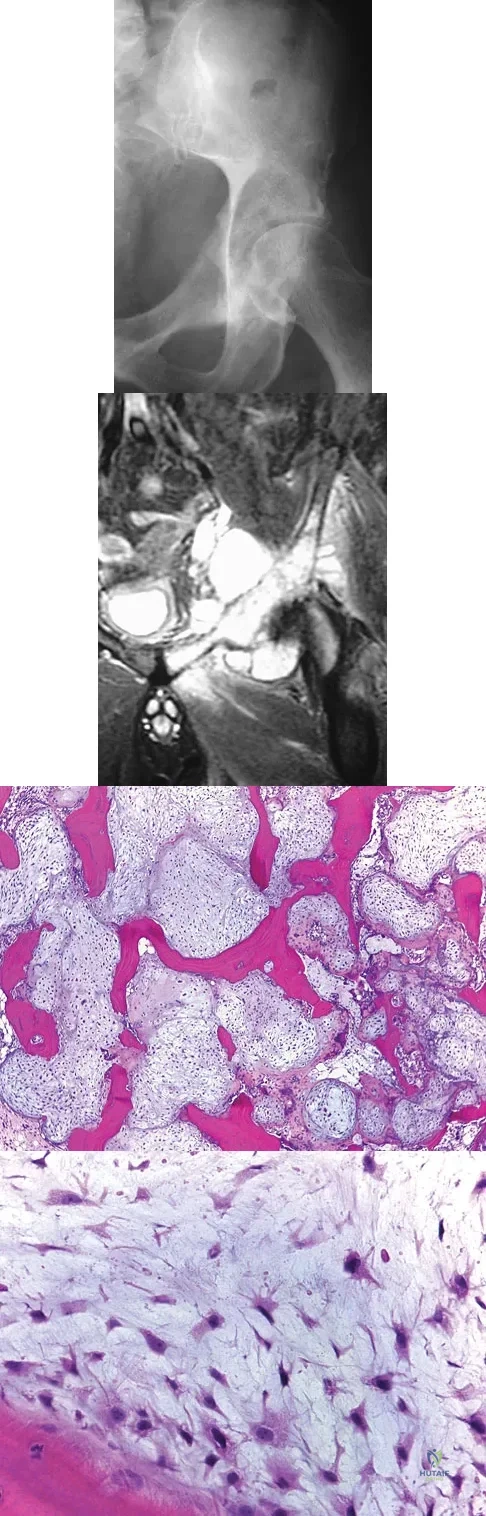

A 64-year-old man has had increasing pain in the left hip for the past 6 months. A radiograph and MRI scan are shown in Figures 25a and 25b. Biopsy specimens are shown in Figures 25c and 25d. What is the recommended treatment?